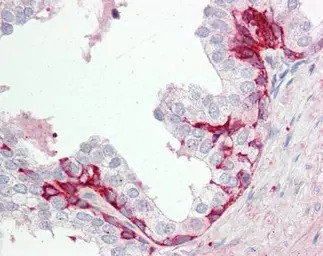

GPR55 antibody [C2C3], C-term detects GPR55 protein at membrane on human prostate by immunohistochemical analysis.

Sample: Paraffin-embedded prostate.

GPR55 antibody [C2C3], C-term (GTX100375) dilution: 1:100.

Antigen Retrieval: Trilogy™ (EDTA based, pH 8.0) buffer, 15min